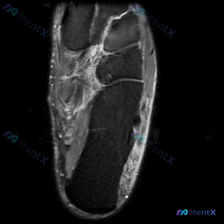

最近碰到一张有意思的读片提问,有人观察到这张足踝MRI里有软组织液信号,整理一下完整的分析思路给大家参考。 病例基础信息 这是一张足部(踝关节远端/后足)的轴位T2加权磁共振图像,我们先梳理图像上的所有信息: 1. 骨骼结构:可见距骨、跟骨截面,轮廓完整,无骨皮质中断或明显形态改变,骨髓信号正常,无...

看到这例足踝的影像资料,整理了观察和分析思路分享给大家。 病例影像基础信息 这是一份足部轴位(横断面)T2加权MRI影像,层面为踝关节远端/跗骨区域: 1. 骨性结构:中央距骨髓腔信号均匀,皮质连续,未见明显异常信号 2. 关节改变:关节间隙可见少量T2高信号,提示存在关节积液,关节面软骨无明显大面...